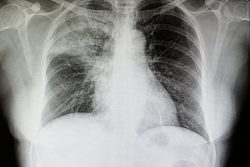

Инфильтрация легких: что это такое, при каких заболеваниях встречается

Инфильтрация легких — пропитывание их ткани воспалительной или иной жидкостью, что приводит к уменьшению дыхательной поверхности и проявляется одышкой и кашлем. Синдром легочной инфильтрации имеет характерные аускультативные и рентгенологические признаки.